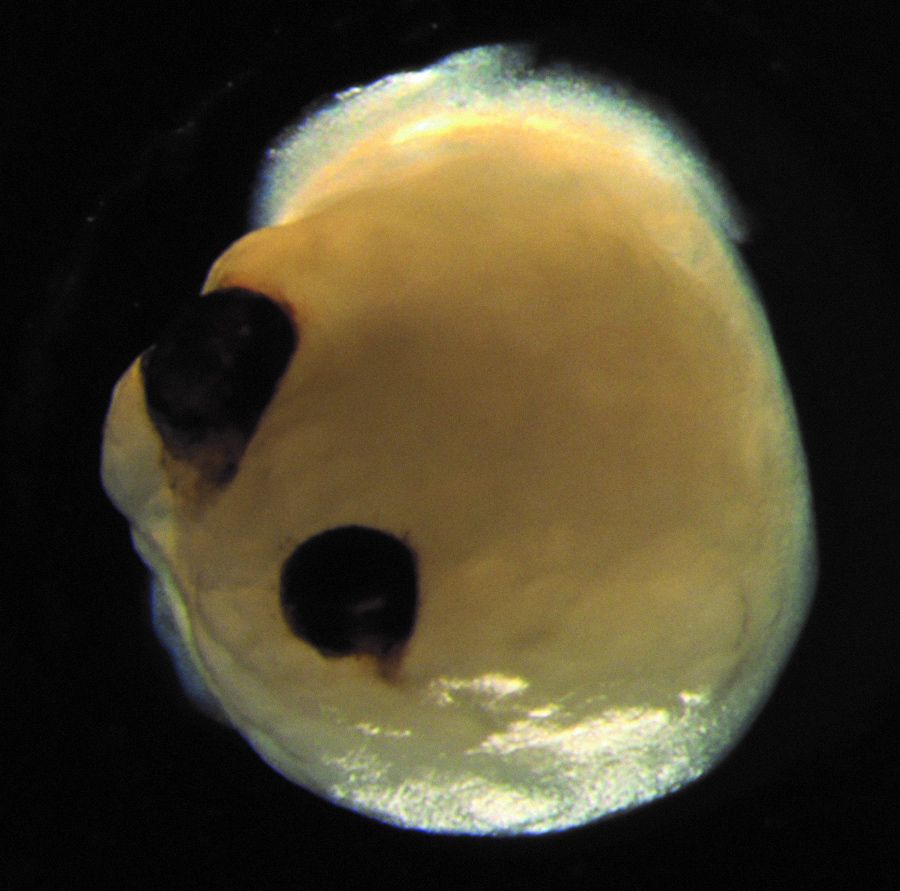

Недавно ученые из Университета Дюссельдорфа рассказали о первом опыте выращивания в пробирке миниатюрной копии человеческого мозга, оснащенной примитивными глазами. Задача эксперимента пока ограничивалась демонстрацией самой его возможности, но вообще говоря «минимозги» за последние годы стали одной из самых модных и интригующих тем в самом практическом плане — для поиска новых лекарств. Таких, например, как болезнь Альцгеймера или шизофрения. Считается, органоиды могут прийти на смену мышам и другим животным, на которых воспроизвести «слишком человеческие» заболевания до сих пор не удавалось. О том, что полезного могут дать довольно странные эксперименты с «мозгами в пробирке», рассказал «Медузе» Алексей Рогожников, сотрудник калифорнийского стартапа Herophilus, который пришел в биотех не из биологии, а из Школы анализа данных «Яндекса» и занимается в стартапе разработкой методов машинного обучения. Алексей рассказал научному редактору «Медузы» Александру Ершову о том, что общего между данными коллайдеров ЦЕРН и активностью нейронов органоидов, и о том, сможет ли миниатюрный мозг-в-пробирке побить рекорды IQ.

С одной стороны, «мини-мозг» это действительно самое близкое короткое словосочетание, которое я могу подобрать для описания того, что мы выращиваем. Но с другой — это тоже не вполне правда, ведь мы не пытаемся смоделировать полноценный мозг, вместо этого церебральные органоиды обычно нацеливаются на какую-то конкретную часть головного мозга.